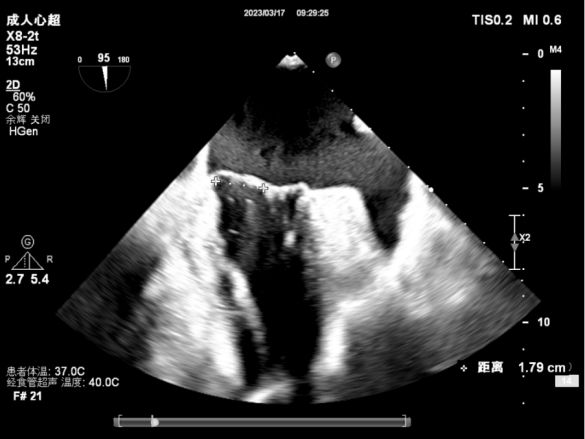

3D测量二尖瓣瓣口面积4.50cm² 病变宽度为1.79cm